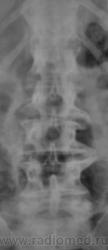

Спондилолистез L5-S1 - истинный, поэтому природа сама набедокуривши, сама и оберегает. Трудно представить безсимптомное течение, если бы это было последствием травмы. Очень рад, что Андрей Юрьевич приводит выдержки из Рейнберга. Судя по желтизне страниц - это первое издание.

По данному случаю:на мой взгляд, он является примером того, что попытки обяснить клинику(страдания пациента) только изменениями на R-граммах несостоятельны (если бы, у пациентки были жалобы,скажем на боли в области поясницы, сделали бы вывод-"что вы хотите?!-деформирующий спондилёз, да ещё спондилолистез- из-за этого и болит"). Думаю, многие сталкивались такими направлениями: "Направляеться на R-графию пояснично-крестцового отдела позвоночника.D.S.:Исключить остеохондроз ".